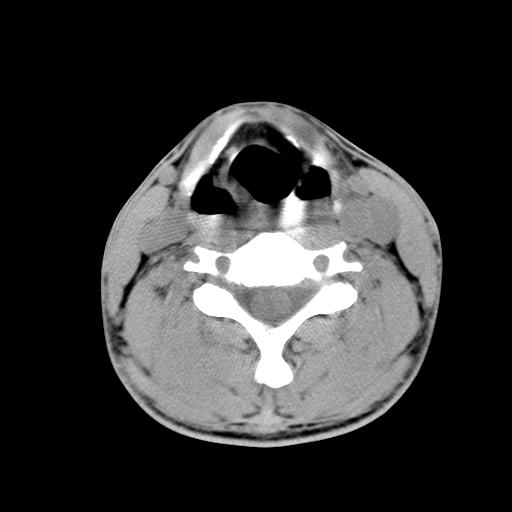

标题: CT15118:f-27y,左颈部肿一个月,无发热、无压痛 [打印本页]

标题: CT15118:f-27y,左颈部肿一个月,无发热、无压痛

1、甲状腺左叶病变:腺瘤?结节性增生?其他?

2、上极周围间隙病变。

3、2者关系?

结节性增生

结节性甲状腺肿

考虑结节性甲状腺肿;建议必要时行进一步检查。